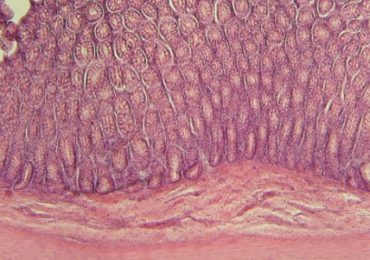

Intolérance au lactose: faut-il supprimer les produits laitiers?

Le sujet est largement débattu depuis quelques années, en particulier sur Internet. Entre confusion, interprétation et désinformation, le lait et ses…

Pré- et probiotiques chez le nourrisson: importance du momentum

La recherche sur les probiotiques et les prébiotiques suggère un ensemble d’effets potentiels bénéfiques pour la digestion du nourrisson. Cependant, les eff…